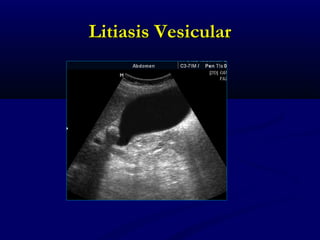

LITIASIS VESICULARLITIASIS VESICULAR

 LITIASIS VESICULARLITIASIS VESICULAR

 Cálculos, con sombra acústica posteriorCálculos, con sombra acústica posterior

 Sensibilidad 97%Sensibilidad 97%

 Cálculos > 2mmCálculos > 2mm

 20% De la población20% De la población

 Obesidad, embarazo, mas frecuente mujeresObesidad, embarazo, mas frecuente mujeres

Criterios ecograficos de litiasisCriterios ecograficos de litiasis

vesicularvesicular

 Focos eco génicosFocos eco génicos

 Sombra acústicaSombra acústica

posteriorposterior

 MovilidadMovilidad

Litiasis vesicular: Sombra acústicaLitiasis vesicular: Sombra acústica